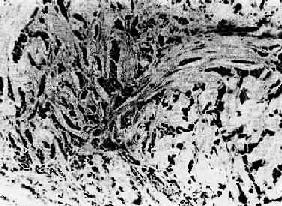

图7-13 腺癌(胃) 癌细胞排列紊乱,多层,形成大小不等、形状不规则的腺样结构,浸润于胃壁组织内 (2)粘液癌(mucoid carcinoma):又称为胶样癌(colloid carcinoma),常见于胃肠。镜下,初时粘液聚积在癌细胞内,将核挤向一侧,使该细胞成印戒状, 故一般称之为印戒细胞(signet-ring cell)。以后粘液堆积在腺腔内,并可由于腺体的崩解而形成粘液池。此时,往往可见于小堆或散在的印戒状癌细胞漂浮其中。肉眼观,癌组织呈灰白色,湿润,半透明如胶冻样,胶样癌因而得名。 (3)实性癌(solid carcinoma):或称单纯癌(carcinoma simplex),属低分化的腺癌,恶性程度较高,多发生于乳腺,少数可发生于胃及甲状腺。癌巢为实体性,无腺腔样结构,癌细胞异型性高,核分裂像多见。有的癌巢小而少,间质结缔组织多,质地硬,称为硬癌(scirrhous carcinoma)(图7-14)。有的则癌巢较大较多,间质结缔组织相对较少,质地如脑髓,称为髓样癌(medullary carcinoma)。

图7-14 乳腺硬癌 癌细胞呈条索状排列,间质丰富,由多量纤维组织构成